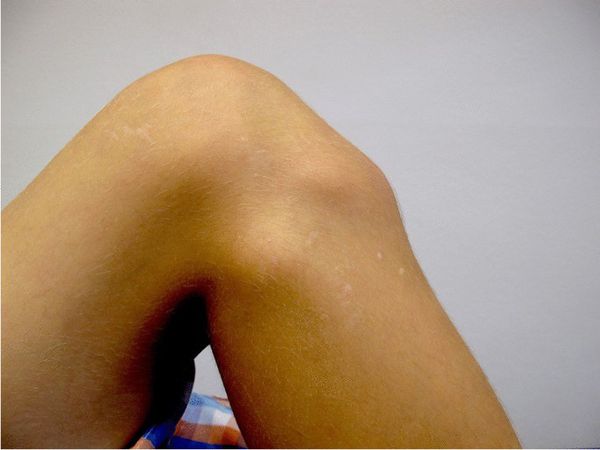

При частых сгибаниях коленного сустава в месте бугристисти большеберцовой кости может появиться твёрдый на ощупь бугорок. Кроме выпячивания пациента ничего не беспокоит.

![Бугорок под коленом [18]](/pimg3/rentgenogramma-pri-bolezni-D970C.jpeg)

Болезнь Шляттера приводит к перестройке бугристости, нестабильности коленного сустава и напряжению мягких тканей ног, из-за чего у людей возникает боль под коленным суставом уже во взрослом возрасте.

Если вовремя не начать лечение острой стадии, часть кости может оторваться. Отрывной перелом сопровождается резкой болью в коленном суставе, отёком и гематомой [10] [13] [15] .